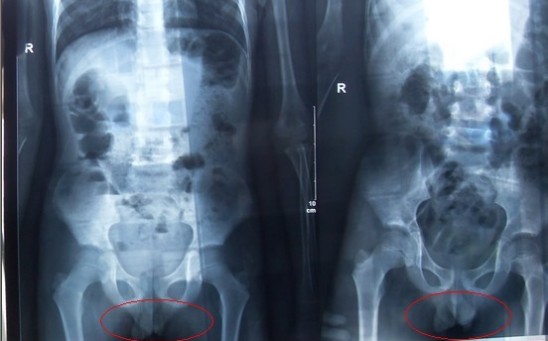

腹部立臥位X光片圖

2011年5月29日下午,陳先生的兒子安安出現(xiàn)嘔吐、肚子疼痛等癥狀。陳先生立即將兒子送往醫(yī)學院附院,根據(jù)醫(yī)生開出的會診單,分別對安安做了腹部立臥位2次和胸部正位1次共3次X光片檢查、診斷。醫(yī)生看X光片后排除了腸梗阻病因,判斷是闌尾炎。經(jīng)過治療,不久安安身體痊愈。

可是,陳先生的一次偶然發(fā)現(xiàn),讓他們一家過上了提心吊膽的日子。因為,在安安出院一個月后,陳先生偶然翻出孩子治療期間的X光片。發(fā)現(xiàn)在X光片中,孩子的生殖器官以及甲狀腺等敏感部位也在被放射區(qū)域中。而陳先生上網(wǎng)查到:人體拍攝X光片是有一定輻射的,并且輻射有可能引起基因變異等問題,他立馬陷入恐慌中。

至于,為什么拍攝X光時,孩子的敏感部位也在放射區(qū)域內(nèi),這讓陳先生百思不得其解。為此,他專門到醫(yī)學院進行了質(zhì)疑。而醫(yī)院的醫(yī)務人員說,拍腹部X光片就要照到睪丸,要檢查睪丸是否正常,而且怕小孩亂動,所以要照寬些。